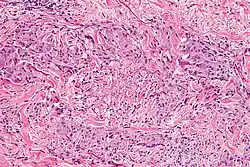

Granuloma annulare microscopically consists of dermal epithelioid histiocytes around a central zone of mucin—a so-called palisaded granuloma.[4]